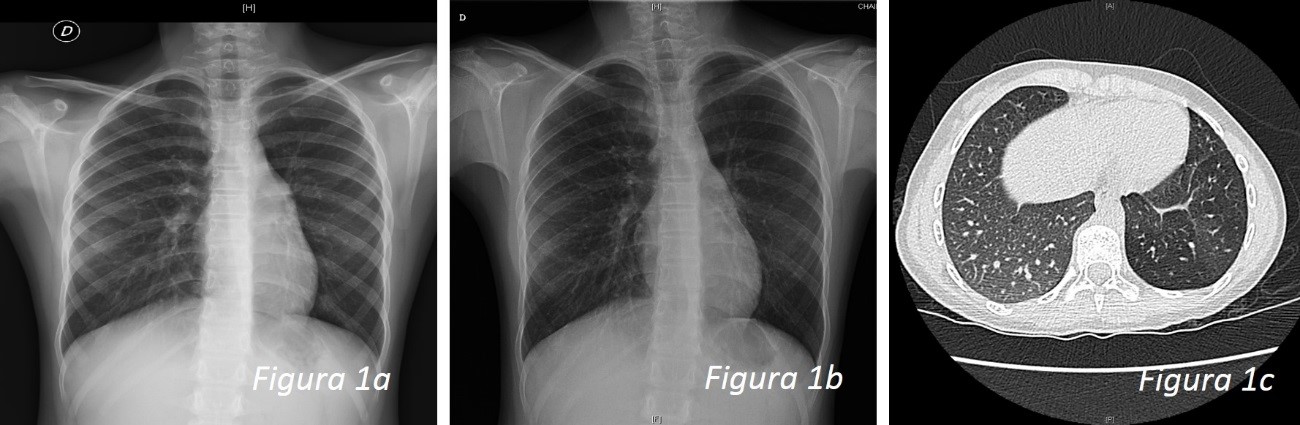

Niña de siete años, nacida en nuestro país, con antecedentes de ingreso neonatal no prolongado por síndrome de aspiración meconial. Presentó una bronquiolitis a los siete meses y posteriormente varios episodios de bronquitis, a los dos, tres y cinco años. Tras uno de los episodios, a los dos años, es diagnosticada de neumonía en el LII que mejora clínicamente con tratamiento antibiótico. A los siete años presenta un nuevo episodio de neumonía en la misma localización, que de nuevo mejora con antibioterapia oral, desapareciendo la fiebre, pero manteniendo saturación de oxígeno algo disminuida (95-96%) y sin llegar a normalizar la auscultación, por lo que precisa administración de salbutamol prácticamente diaria. En ambos procesos presenta imagen radiológica de consolidación-atelectasia en LII (Figs. 2a y 2b). Se realiza: Mantoux con resultado de 0 mm, estudio inmunológico básico normal con aumento de IgE, y determinación de α-1-antitripsina normales.

Dada la persistencia de subcrepitantes y sibilancias en la base izquierda, y la necesidad de salbutamol diario tras el segundo episodio de neumonía, se deriva a Rehabilitación y Neumología Pediátrica, donde se realiza la espirometría en la que se muestra una función pulmonar en el límite inferior de la normalidad en cuanto a FEV1, y pruebas de alergología positivas para pólenes. Se instaura tratamiento con budesonida y ante la persistencia de clínica se realiza una TC torácica (Fig. 2c) que muestra un aumento de la atenuación en el parénquima del LII, localizado entre los segmentos 8-9, sin aparentes alteraciones bronquiales centrales, aunque con algunas zonas irregulares adyacentes, con una gran arteria procedente de la aorta torácica, a la altura de D10, que irriga dicha zona del LII, que parece drenar a las venas pulmonares, sugestivo de secuestro pulmonar.

| Figura 2. Caso clínico 2: a) edad 2 años: imagen radiológica de consolidación-atelectasia en el LII; b) edad 7 años: imagen radiológica de consolidación-atelectasia en LII; c) TC: aumento de la atenuación en el parénquima del LII, segmentos 8-9, sin aparentes alteraciones bronquiales centrales, con una gran arteria procedente de la aorta torácica, a la altura de D10, e irriga dicha zona de LII |